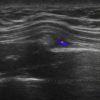

Gãy xương sườn

» Thông tin: Nữ giới – 52 tuổi.

» Lâm sàng: Chấn thương ngực.